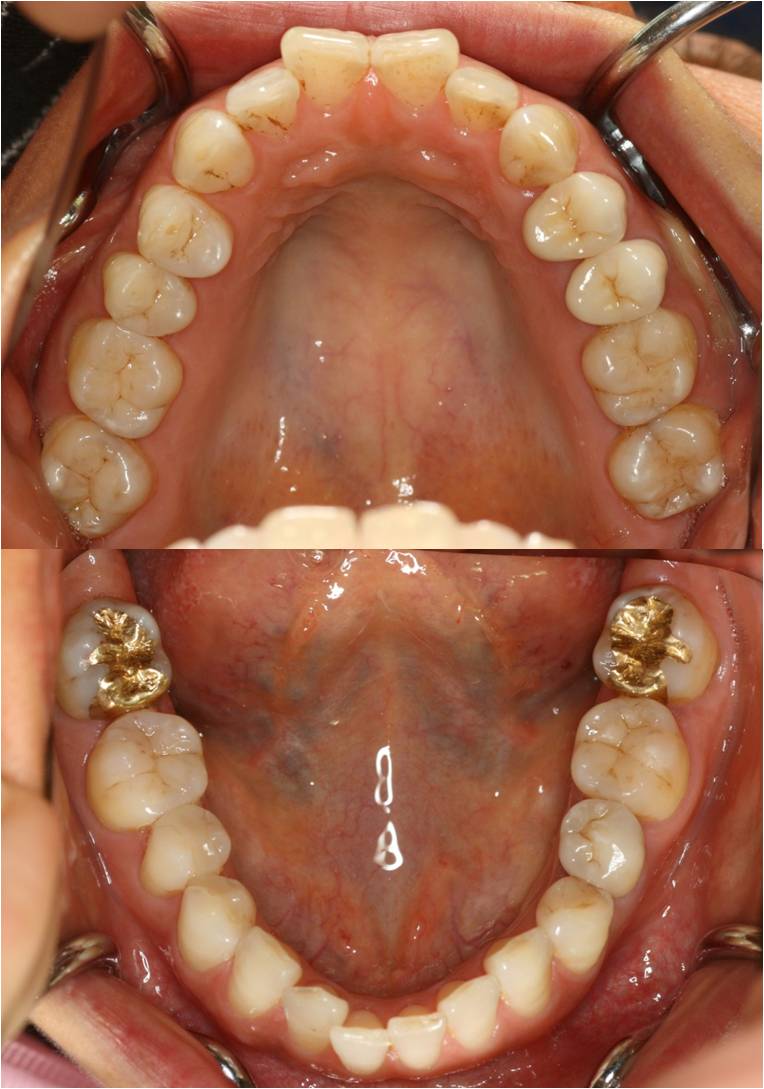

術後

http://www2.ha-channel-88.com/bbs/upimg/?l=2963

・エンド

・レジン

・ジルコニア(セラミック)

・ゴールド修復